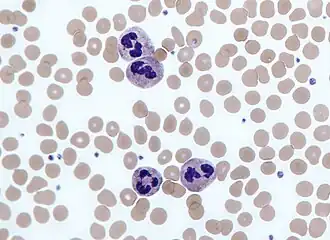

Neutrophils are normally found in the bloodstream and are the most abundant type of phagocyte, constituting 50% to 60% of the total circulating white blood cells.[77] One litre of human blood contains about five billion neutrophils,[3] which are about 10 micrometers in diameter[78] and live for only about five days.[39] Once they have received the appropriate signals, it takes them about thirty minutes to leave the blood and reach the site of an infection.[68] They are ferocious eaters and rapidly engulf invaders coated with antibodies and complement, and damaged cells or cellular debris. Neutrophils do not return to the blood; they turn into pus cells and die.[68] Mature neutrophils are smaller than monocytes and have a segmented nucleus with several sections; each section is connected by chromatin filaments—neutrophils can have 2–5 segments. Neutrophils do not normally exit the bone marrow until maturity but during an infection neutrophil precursors called metamyelocytes, myelocytes and promyelocytes are released.[79]

The intra-cellular granules of the human neutrophil have long been recognized for their protein-destroying and bactericidal properties.[80] Neutrophils can secrete products that stimulate monocytes and macrophages. Neutrophil secretions increase phagocytosis and the formation of reactive oxygen compounds involved in intracellular killing.[81] Secretions from the primary granules of neutrophils stimulate the phagocytosis of IgG-antibody-coated bacteria.[82] When encountering bacteria, fungi or activated platelets they produce web-like chromatin structures known as neutrophil extracellular traps (NETs). Composed mainly of DNA, NETs cause death by a process called netosis – after the pathogens are trapped in NETs they are killed by oxidative and non-oxidative mechanisms.[83]